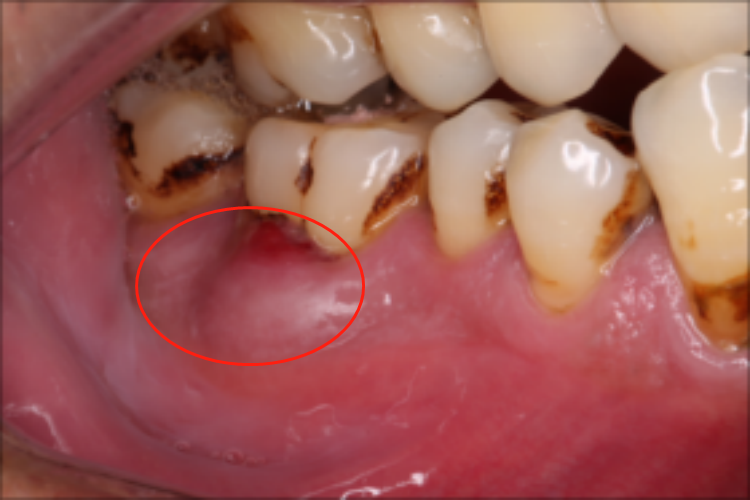

牙槽脓肿

牙槽脓肿一般无牙周袋,且患牙存在龋病、修复体或非龋性疾病等外在刺激,牙髓无活力,脓肿范围较弥散,中心位于龈颊沟附近,疼痛程度较重,牙齿松动较轻,部分可出现剧烈松动,治愈后牙齿可恢复稳固,叩痛明显,病程相对较长。